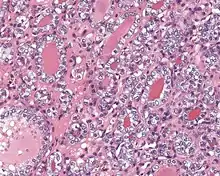

Several specific features must be identified for the tumor to be classified in this new category, while exclusion criteria should also be evaluated.

1) Encapsulated or partially encapsulated. The tumors are usually very well delimited or circumscribed, with the majority encapsulated, surrounded by a well formed fibrous connective tissue capsule.

2) Complete absence of invasion of any kind in a tumor that has been thoroughly and carefully evaluated with the whole capsule of the lesion sampled.

3) Predominantly follicular pattern of growth. Papillary structures should not be present. Further, solid, insular, or trabecular architecture must be <30% of the overall tumor for this category to still apply. Colloid (the material that thyroid follicular cells create) is easily identified throughout.

4) Must have the characteristic nuclear features of papillary thyroid carcinoma, although sometimes the features are patchy in distribution without all of the tumor showing those features. The nuclear features can be divided into three main categories:

- Nuclear size and shape: nuclear enlargement, nuclear elongation, and nuclear overlapping and crowding. Loss of nuclear polarity, with nuclei at the lumen, middle, or basal zone of the cells is also a helpful finding.

- Nuclear membrane irregularities: irregular nuclear contours, nuclear grooves and folds, "rat-bites" or demi-lune formations, and the presence of intranuclear cytoplasmic inclusions.

- Nuclear chromatin characteristics: nuclear chromatin clearing, often with condensation or margination along the nuclear membranes, resulting in accentuated nuclear margins, glassy nuclei, or fine, even delicate, powdery nuclear chromatin.

These features have been recently validated by an international group of practicing general surgical pathologists, showing a substantial interobserver agreement with applying a Nuclear Standardized Scoring System.[17]